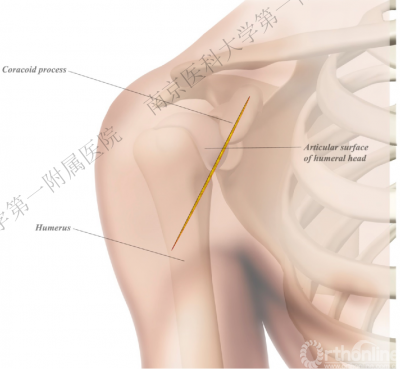

二、损伤机制

暴力始于肱骨头后关节面,随暴力增加累及周围结构,最终导致肱骨近端骨折。

四、分型

肩关节后脱位:

Ⅰ型: +肱骨颈骨折。

Ⅱ型: +肱骨颈骨折+小结节骨折(病例3)。

Ⅲ型: +肱骨颈骨折+小结节骨折+大结节骨折(病例2),以骨折线向肱骨近端外侧壁延伸为另一特征。